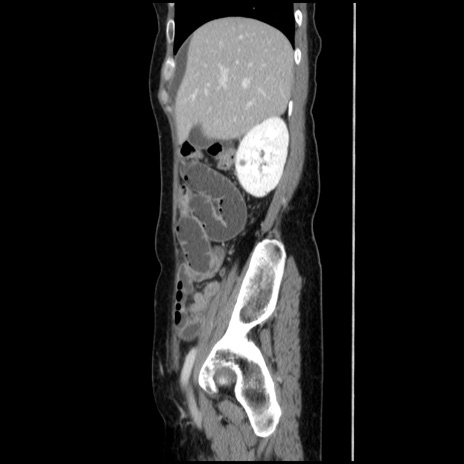

横断像

【症例】40歳代 女性

【主訴】上腹部痛、嘔気・嘔吐

【現病歴】約9時間前頃から急に上腹部痛、嘔気、嘔吐が出現。改善しないため救急要請。

【既往歴】子宮頚癌(広汎子宮全摘術、放射線療法)、腸閉塞

【身体所見】腹部:平坦、軟、腸雑音亢進、上腹部を中心に腹部全体に圧痛あり。

【データ】WBC 8400、CRP 0.03